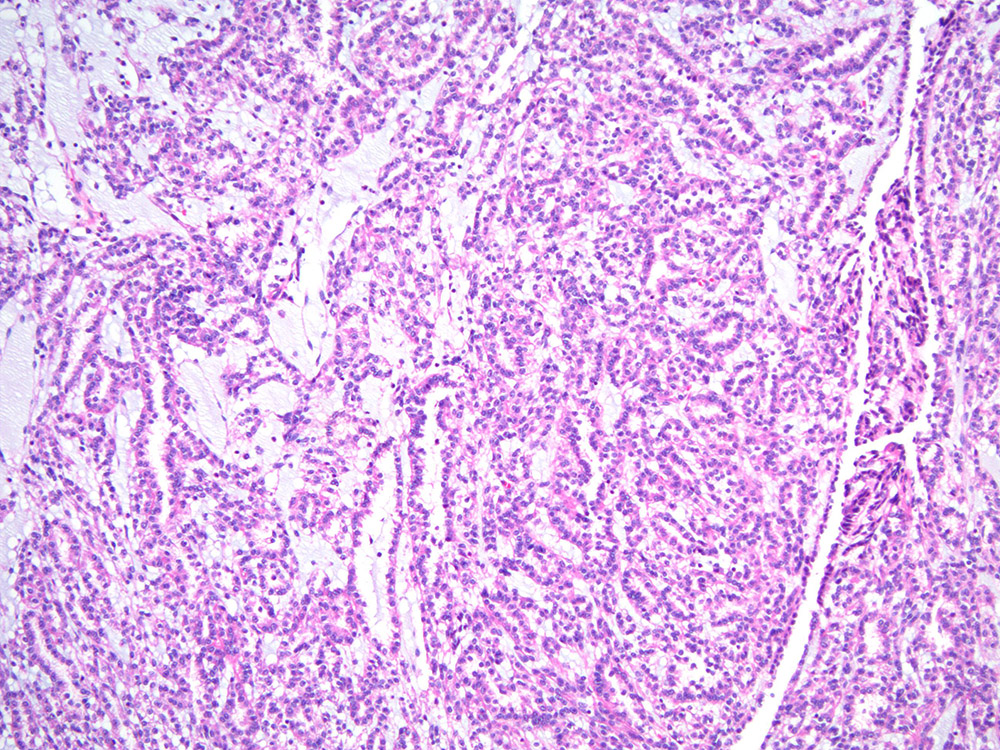

Classification of renal tumors

Case ID: 315